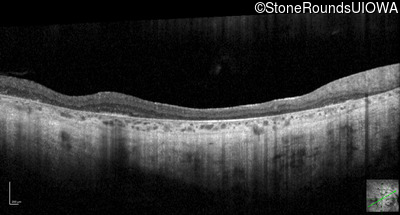

Optical Coherence Tomography - Left - 10/225

Exemplar / OCT Stack